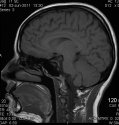

I have attached my own brain MRI to show the proximity of the brain to the front of the skull. As you can see from the front of the skull to the frontal lobe is mere centimeters. (Also in between the brain in the skull is filled with CSF and also large veins that would cause major bleeding. It's not just some ley-way site where everything's fine if you hit that area.). It was said the bullet entered from the right forehead above the brow and lodged in the left cheek. If you did a trajectory on an actual anatomical depiction of a brain MRI it would seem that it would have to enter the brain in order to lodge where it did, as the medical examiner stated. Also if it did not it would pierce through the optic nerves leaving TA unable to see. Also gun shot wounds cause skull fractures upon entry and it's a high impact force causing concussive damage and shock to the brain that injures parts of the brain that were never touched by the bullet. I just think TA would have been unable to travel as far as he did with a gun shot wound to the face at such close range. Also if you study forensic pathology close range gun shot wounds leave burnt on shoot and burn wounds to the skin around the site of entry. It is debatable how close she would have shot him though I guess. I also think it's very telling that the medical examiner didn't find much blood inside the cranial cavity which would be indicative of the victim having bled out prior to the shot as otherwise much bleeding would have occurred as the scalp, facial area, eyes, and frontal lobe have extensive blood supply. Also I believe the medical examiner is the person that would know for certain whether the bullet entered the brain or not. He has seen inside of TA's cranial cavity. Even though the brain was too decomposed to examine the bones do not decompose. He would have been able to see the trajectory through the bones, it would have had to enter the cranial cavity and exit the cranial cavity into the cheek to hit the brain. I just can't imagine that it would just go through TA's sinuses and not enter his cranial cavity at all and this ME not be able to tell the difference in bony trajectory that never decomposes. There can be no error in that. This is why I believe TA was shot last. All MOO and JMO.

I have attached my own brain MRI to show the proximity of the brain to the front of the skull. As you can see from the front of the skull to the frontal lobe is mere centimeters. It was said the bullet entered from the right forehead above the brow and lodged in the left cheek. If you did a trajectory on an actual anatomical depiction of a brain MRI it would seem that it would have to enter the brain in order to lodge where it did, as the medical examiner stated. Also if it did not it would pierce through the optic nerves leaving TA unable to see. Also gun shot wounds cause skull fractures upon entry and it's a high impact force causing concussive damage and shock to the brain that injures parts of the brain that were never touched by the bullet. I just think TA would have been unable to travel as far as he did with a gun shot wound to the face at such close range. Also if you study forensic pathology close range gun shot wounds leave burnt on shoot and burn wounds to the skin around the site of entry. It is debatable how close she would have shot him though I guess. I also think it's very telling that the medical examiner didn't find much blood inside the cranial cavity which would be indicative of the victim having bled out prior to the shot as otherwise much bleeding would have occurred as the scalp, facial area, eyes, and frontal lobe have extensive blood supply. Also I believe the medical examiner is the person that would know for certain whether the bullet entered the brain or not. He has seen inside of TA's cranial cavity. Even though the brain was too decomposed to examine the bones do not decompose. He would have been able to see the trajectory through the bones, it would have had to enter the cranial cavity and exit the cranial cavity into the cheek to hit the brain. I just can't imagine that it would just go through TA's sinuses and not enter his cranial cavity at all and this ME not be able to tell the difference in bony trajectory that never decomposes. There can be no error in that. This is why I believe TA was shot last. All MOO and JMO.